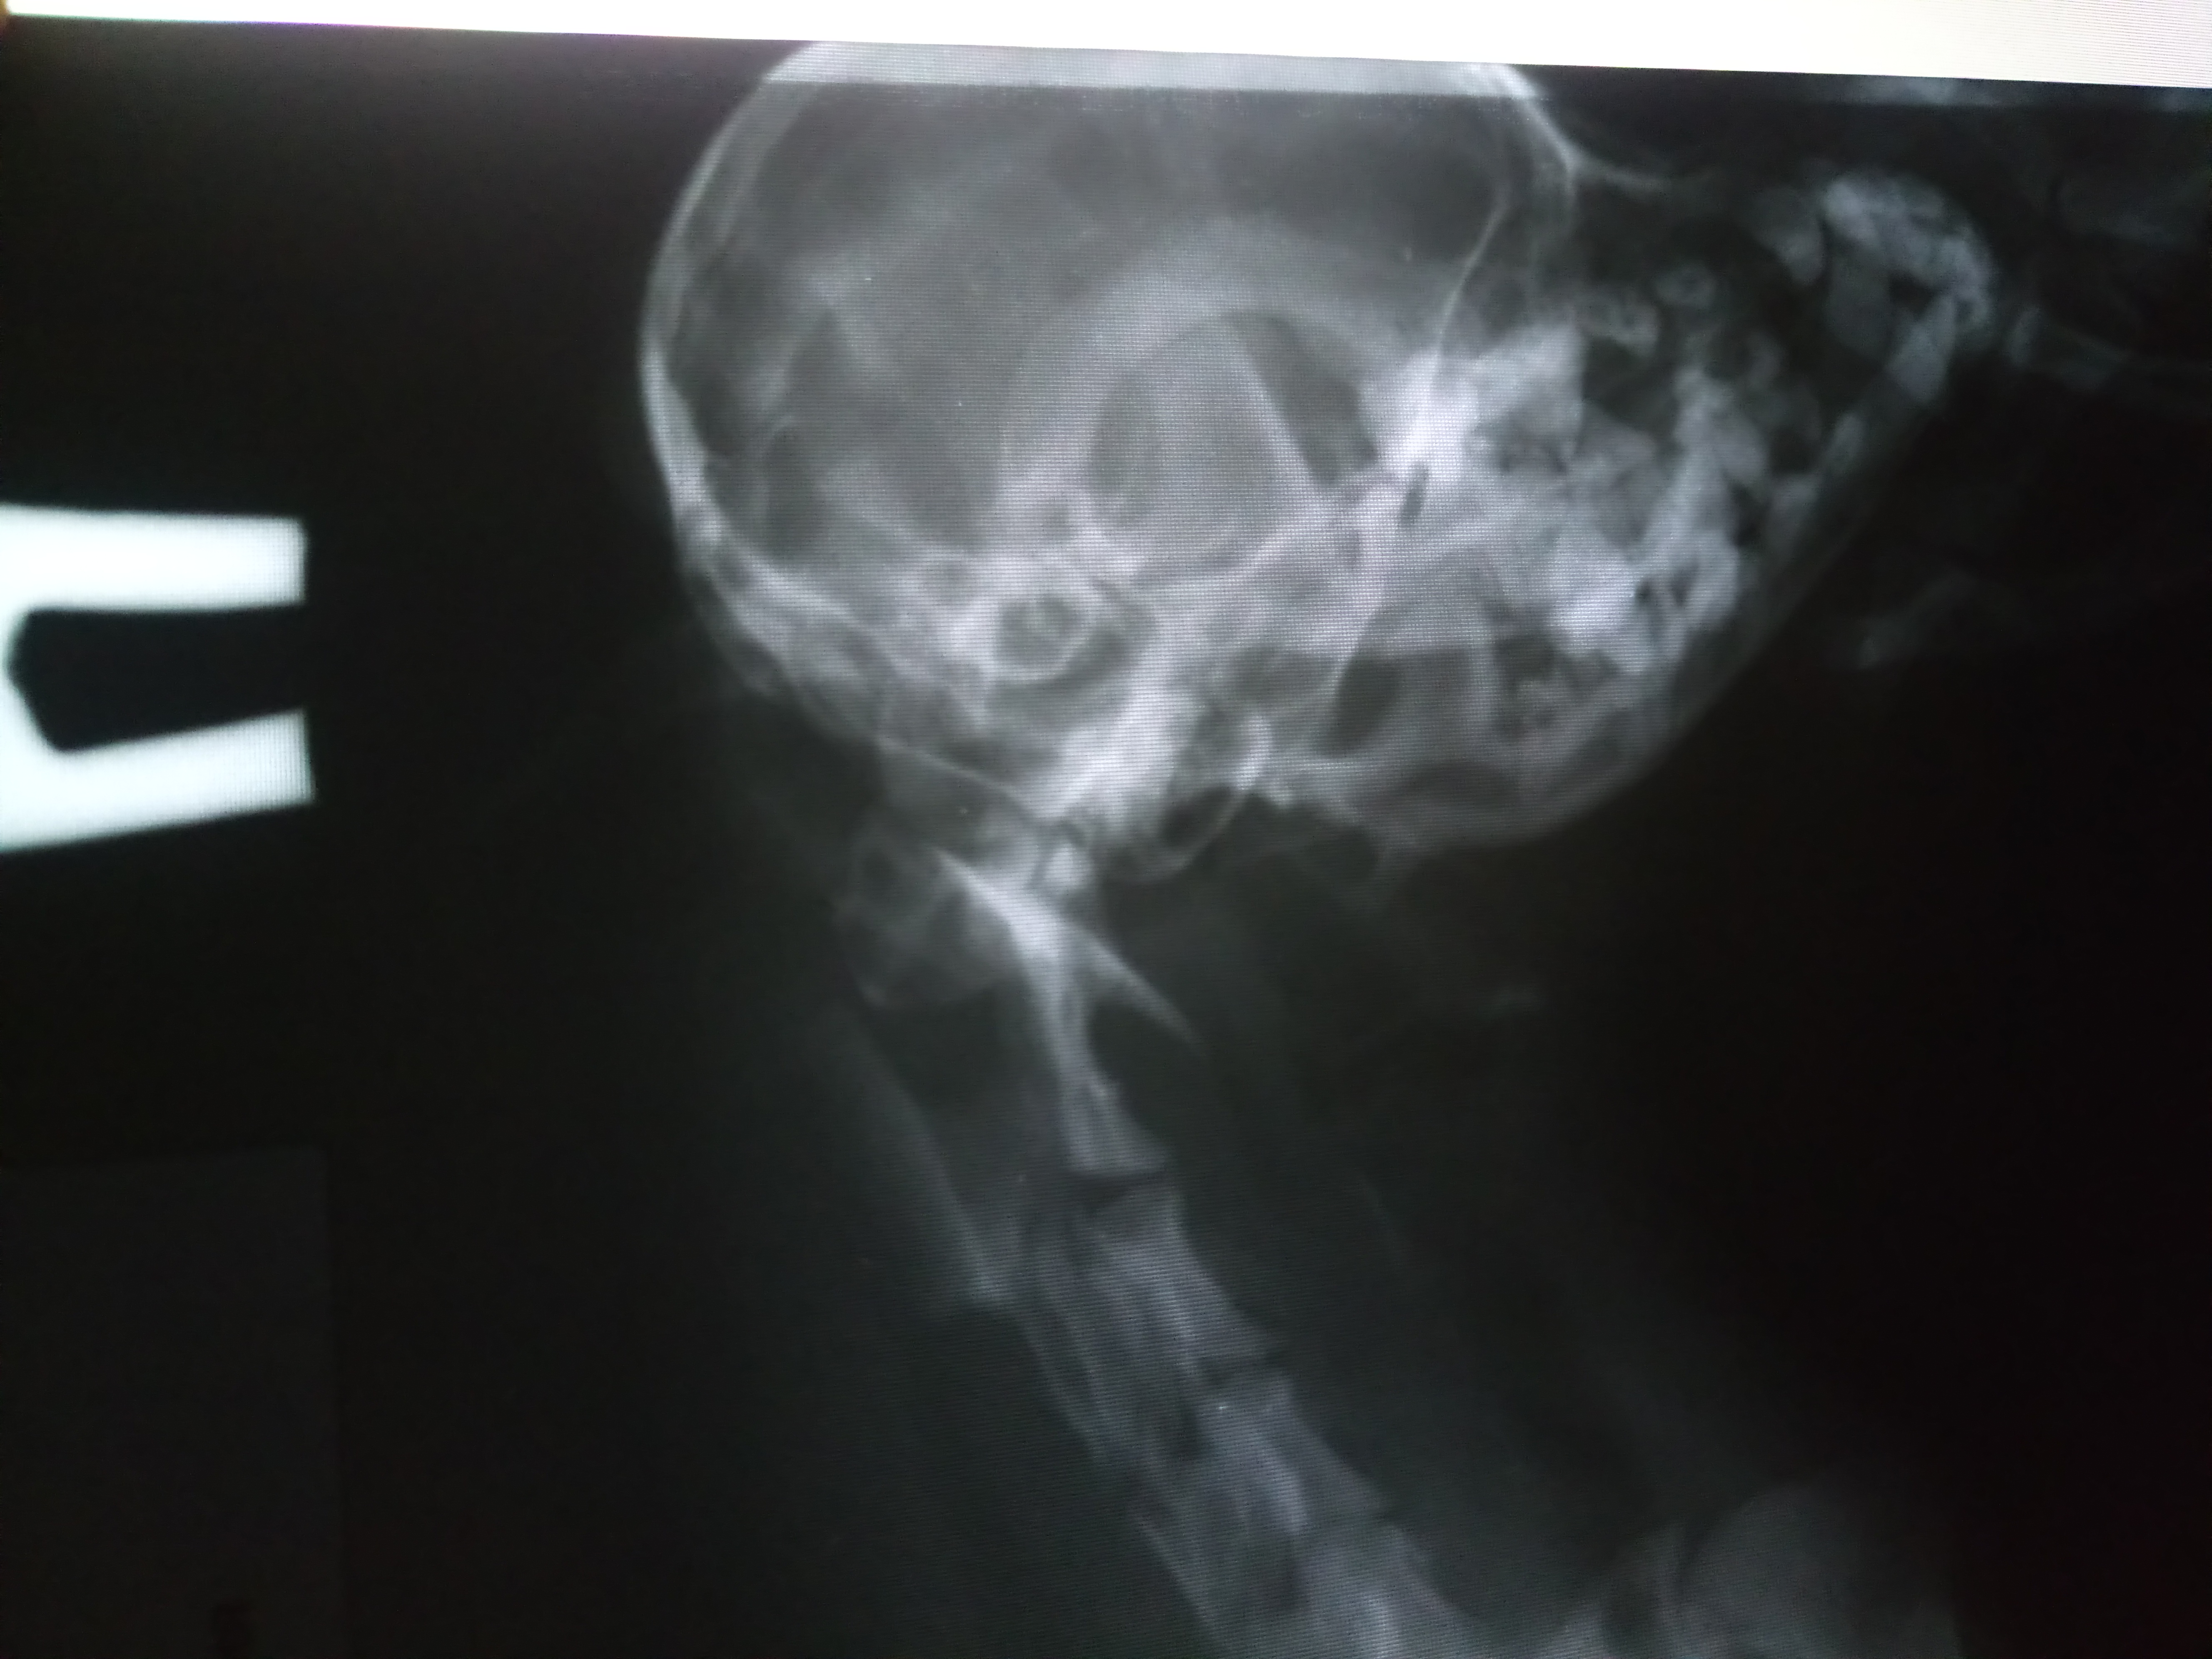

Может быть кто-то подскажет по снимку, если это возможно?

Снимки лучше отсылать специалистам для консультации

Viktoriya, Сотников снимки видел. Что он видит на снимке-цитирую-собаку карликовой породы. Потом добавил-ничего больше нельзя увидеть, переломов больших нет, опухолей больших нет, инородных рентгеноконтрастных тел нет

Viktoriya, ортопед иногородней клиники усмотрел вот такую картину-Похоже есть разрыв атланто-окципитальной мембраны. Отхождение тени атланта от тени черепа, что говорит о компресии спинного мозга по передней поверхности и неполном разрыве задних канатиков. Исходя из клиники прогноз неблагоприятный в плане восстановления.

Но Сотников не согласился с их диагнозом